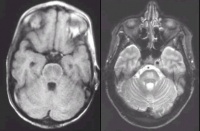

2.必要时做脑CT检查。